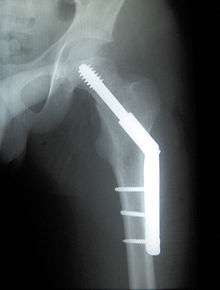

Dynamic hip screw

Dynamic hip screw (DHS) or Sliding Screw Fixation is a type of orthopaedic implant designed for fixation of certain types of hip fractures which allows controlled dynamic sliding of the femoral head component along the construct. One common use is internal fixation of intertrochanteric fractures of the femur, which are common in older osteoporotic patients. There are 3 components of a dynamic hip screw, including a lag screw (inserted into the neck of the femur), a sideplate and four cortical screws (fixated into the proximal femoral shaft) The idea behind the dynamic compression is that the femoral head component is allowed to move along one plane; since bone responds to dynamic stresses, the native femur may undergo primary healing: cells join along boundaries, resulting in a robust joint requiring no remodeling.